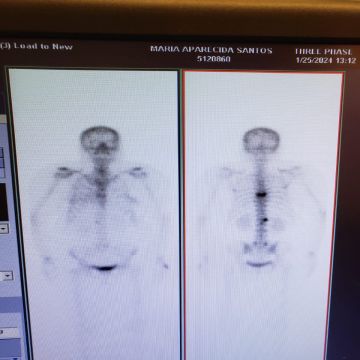

me chamo felipe, tenho 31 anos, trabalho na trabalho na área da saúde como cuidador no brasil, sou técnico de raio x e estudante de biomedicina no brasil